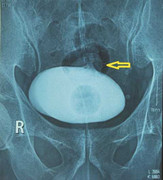

Một bé trai 6 tuổi ở Quảng Ngãi nhập viện vì đại tiện ra máu kéo dài, các bác sĩ phát hiện bé có tới 4 polyp đại tràng, trong đó polyp kích thước lớn hiếm gặp.